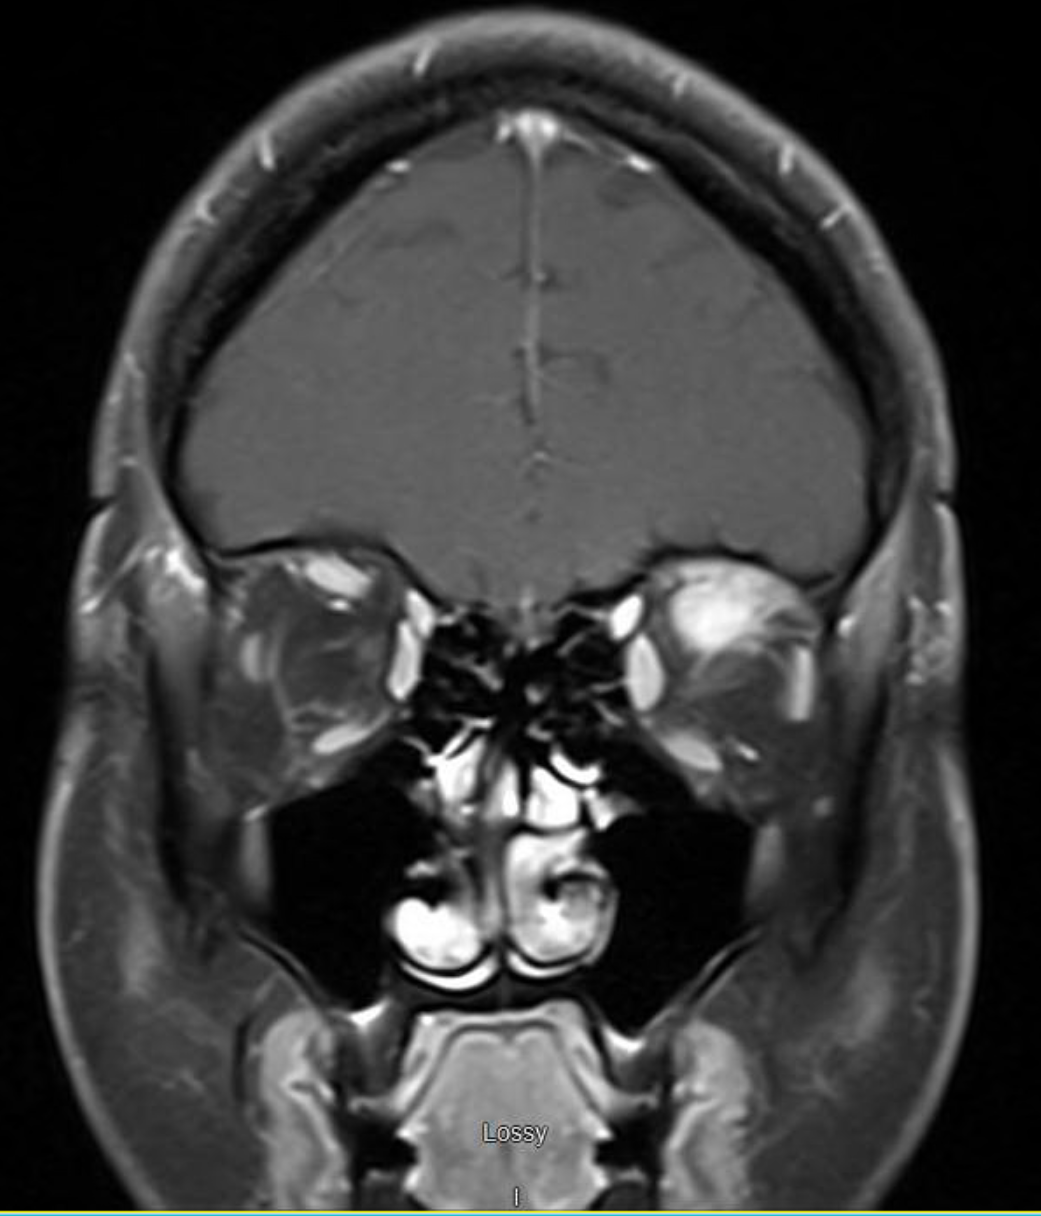

MRI of brain and orbit demonstrated 27x12x8.2 mm mass-like enhancement in the superior part of the left orbit involving the left superior rectus muscle. This exerted mass effect on the infraorbital segment of the left optic nerve. Infectious work up was negative. CT of the neck, chest, abdomen, and pelvis were negative for lymphadenopathy or similar lesions.

Repeat MRI of brain showed regression of the orbital mass.